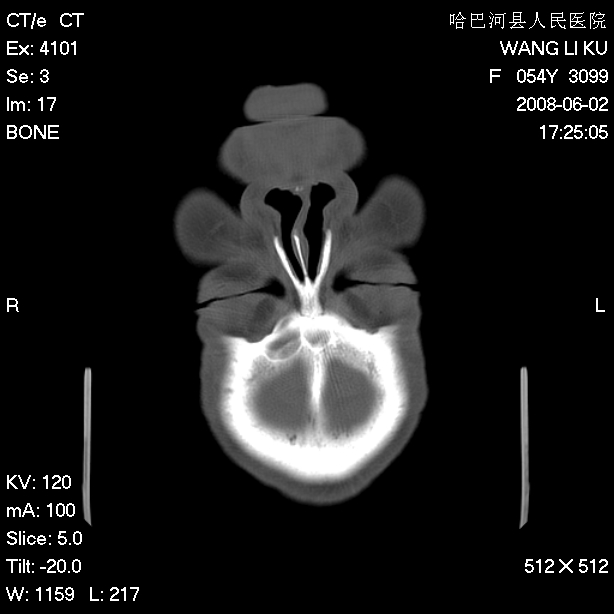

标题: CT13803:反复性鼻塞、流涕一年余 [打印本页]

标题: CT13803:反复性鼻塞、流涕一年余

副鼻窦炎,右上额窦积脓。左眼肌锥内见致密影,视神經受压

1.全组副鼻窦炎2.双侧上颌窦积液

全组副鼻窦炎

1)全副鼻窦炎(左侧上颌窦黏膜下囊肿或息肉)。2)左眼眶肌锥内不规则小结节状软组织密度影;考虑为小血管瘤可能。建议行ct增强扫描检查。

全组副鼻窦炎,左侧肌锥内不规则形软组织肿块影,与眼外肌密度相当,左侧视神经受压,肿块与视神经及眼外肌分界清晰,眼外肌无增粗,眶壁无破坏,球后脂肪间隙不模糊,考虑良性改变,小血管瘤或神经源性肿瘤可能,建议增强扫描。

谢谢,增强扫描做了,眶内病灶与海绵窦同步明显强化,血管瘤